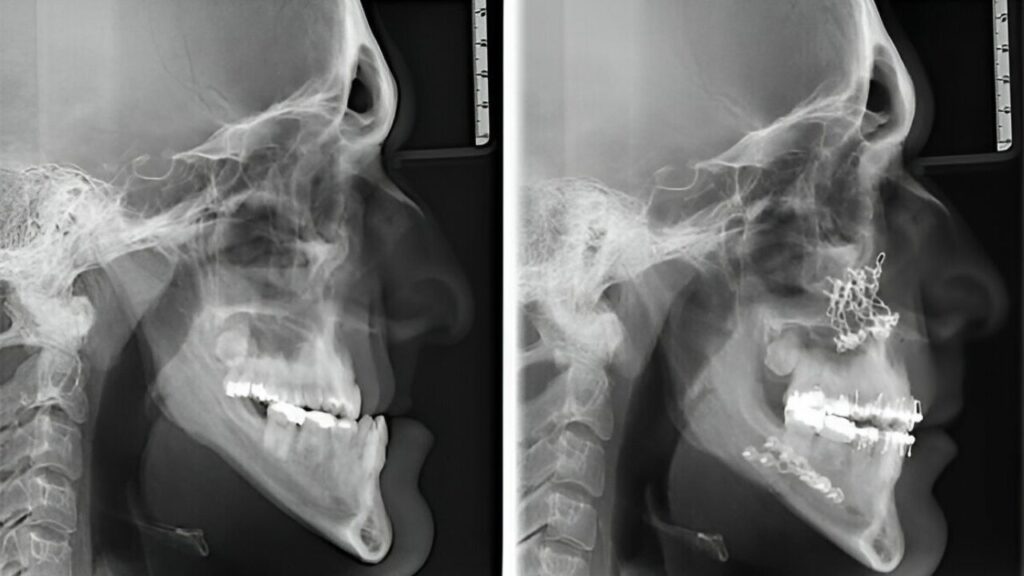

Cirurgia ortognática antes e depois: resultados

Os resultados das cirurgias ortognáticas podem ser impressionantes. Antes do procedimento, o paciente pode apresentar desalinhamentos faciais significativos, problemas de oclusão e autoestima prejudicada.

Além da melhoria estética, os pacientes geralmente experimentam uma restauração significativa da função mastigatória, respiratória e da articulação temporomandibular (ATM). Esses procedimentos não só transformam a aparência facial, mas também melhoram a autoconfiança e a qualidade de vida do paciente.

Após a recuperação completa, que pode levar alguns meses, o paciente geralmente exibe uma melhora notável na harmonia facial, função mastigatória e confiança pessoal.